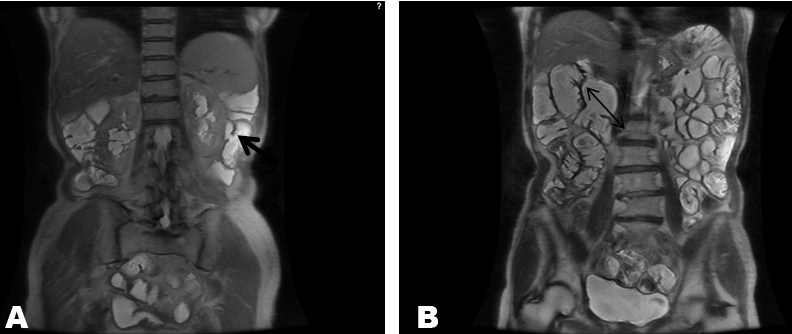

The MRI-Sellink showed multiple small intestine diverticula which were mainly present in the middle part of the abdomen right underneath the abdominal wall (Figure 1A-B). The conventional upper and lower endoscopy could not reach these parts of jejunum and ileum and a double-balloon enteroscopy was not performable due to technical reasons. Conservative management with antibiotics and dietary alterations was initiated. In our case, no satisfying response was reported, so that a surgical intervention was decided. After having the most of her intestine diverticula surgically removed, the patient gained her normal weight again.

Figure 1: (A) The little arrow showing a small intestine diverticulum, (B) Small intestine diverticulum measuring up to 4–5 cm in the middle part of the abdomen.